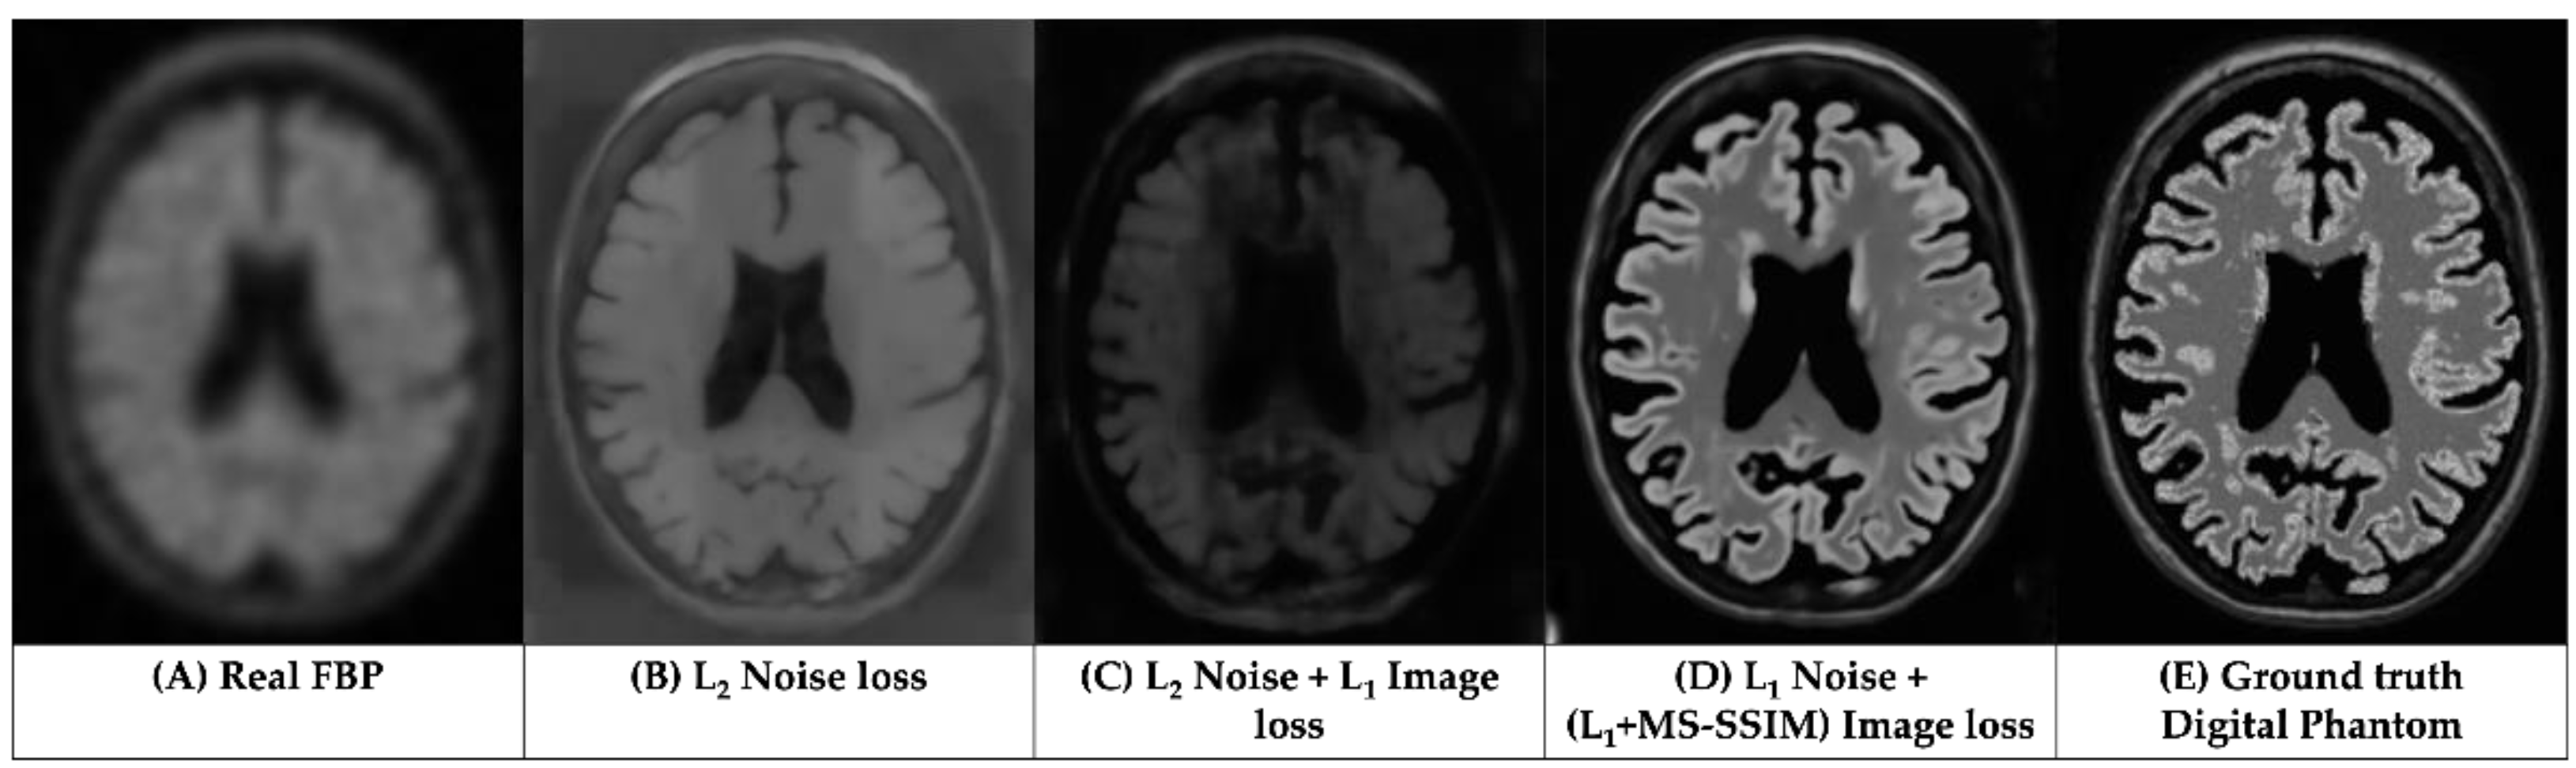

3.1. Qualitative Assessments